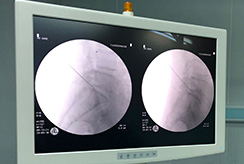

The PLDD treatment is performed on an outpatient basis using only local anesthesia. During the procedure, a thin needle is inserted into the herniated disc under x-ray or CT guidance. An optical fiber is inserted through the needle and laser energy is sent through the fiber, vaporizing a tiny portion of the disc nucleus. This creates a partial vacuum which draws the herniation away from the nerve root, thereby relieving the pain. The effect usually is immediate.

The patient will be instructed to take a prone position on the table of the CT-scan. After placing sterile drapes the level of treatment is identified by a scan. The needle entry point is anesthetized by local lidocaine injection no deeper than the facet joint. Subsequently the 18G needle is placed centrally in the nucleus pulposus, and parallel to the endplates by means of a posterolateral approach. Through the needle, a glass fiber is placed in the disc, enabling the application of laser energy (980 nm, 7 W, 0,6 s pulses, interval 1 second). After a total energy of 1500 J is delivered (2000 J for level L4-5), the PLDD procedure is finished. A control CT scan is performed to assess gas formation in the disc space. After the treatment the patient is allowed to drink tea or coffee and is observed for 15 minutes before he/she can return home. |